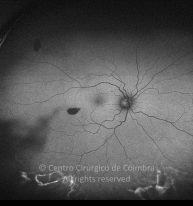

Traumatismo con un clavo en el ojo derecho hace unos 20 años, con perforación de la córnea y del iris. Catarata traumática. MAVC: 20/60 OD; OI ambliope.

Retinografía color

Cicatriz temporal. Antecedentes de vitrectomía con vítreo inferior no removido.